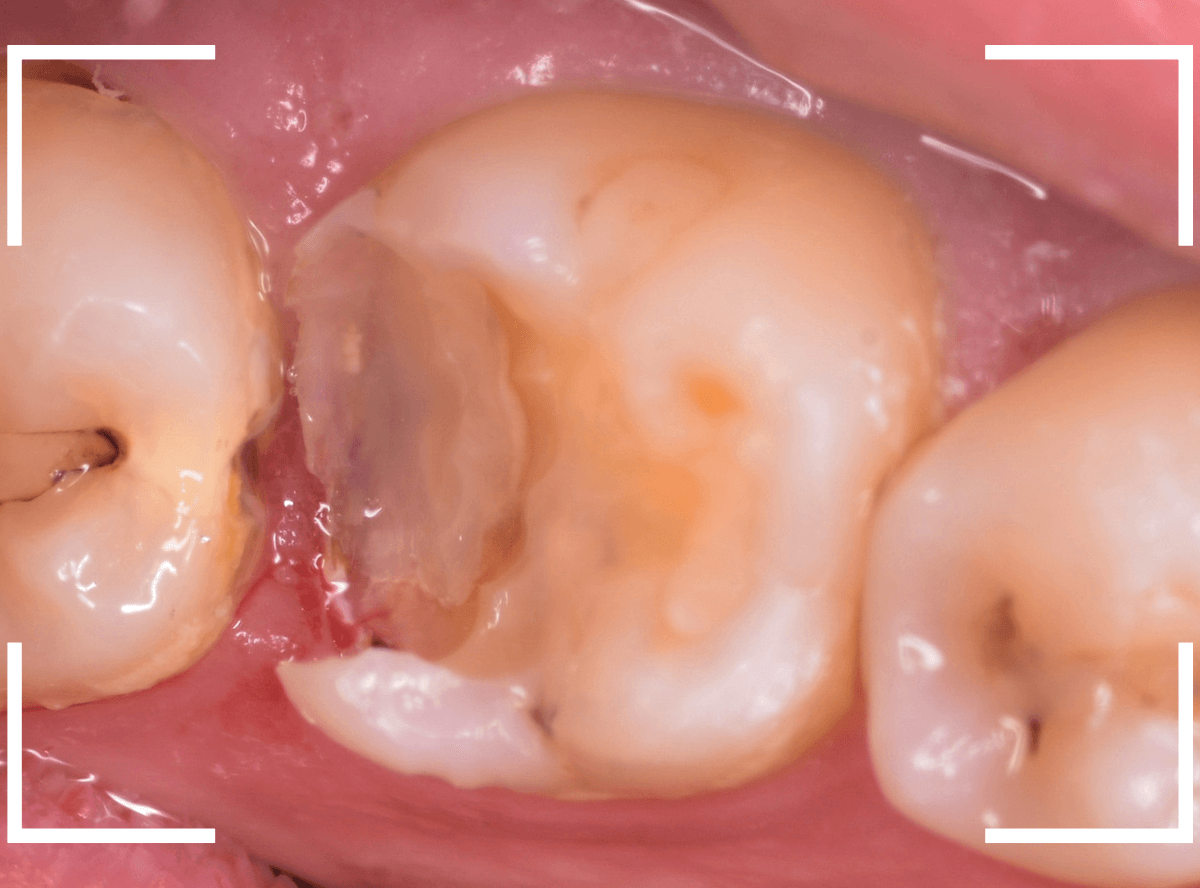

上の小臼歯の側面が明らかに虫歯になっている患者さんです。

患者さんは特に症状を感じてなさそうですが、恐らくは中で大きな虫歯になっているでしょう。

このように、自覚症状からだけでは虫歯の状況は診できません。

まず、奥の歯のつめものを外してから、虫歯の治療を開始します。

手前の歯が大きな虫歯が見えてきました。

神経に達してしまいそうな虫歯ですので、ある程度削ったところで、少しずつエキスカという道具で掻き出すようにして、虫歯を除去します。

虫歯は歯を溶かして進行しますので、骨よりも固い歯もちょっと掻き出すとボロボロと崩れるようになってしまっています。

かなり虫歯を除去したところで、手前の歯は神経が顔を出してしまいました(露髄といいます)。